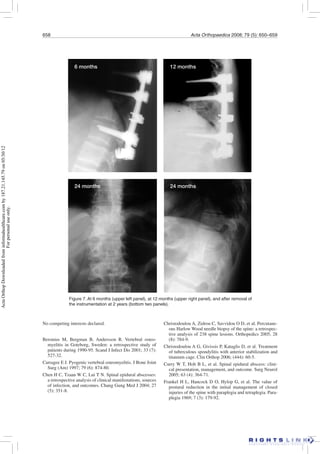

Figure 7. At 6 months (upper left panel), at 12 months (upper right panel), and after removal of

the instrumentation at 2 years (bottom two panels).

6 months 12 months

24 months 24 months